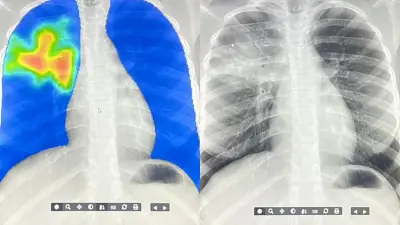

There's a global shortage of radiologists Now artificial intelligence is helping speed up the evaluation of tuberculosis in hard-to-reach communities Image credit ARCAD Sant PLUS